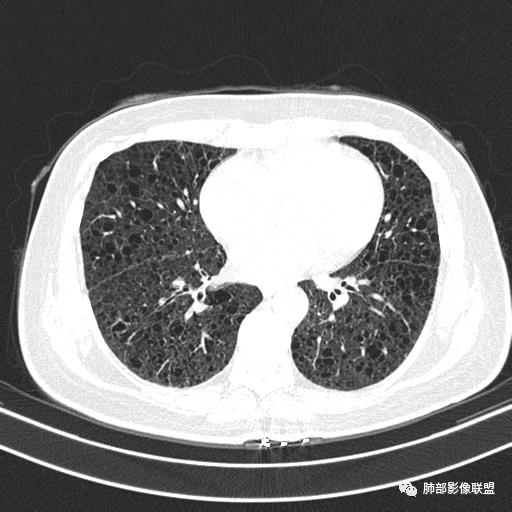

双肺弥漫囊腔,累及肋膈角,囊腔形态相对规则单一。

CT平扫示双肺弥漫分布大小不等囊状薄壁透光区,无内、中、外带分布差异,间质稍示增厚。拟LAM

中年女性育龄期妇女,咳嗽气喘,无吸烟史,有苯吸入史。影像:双肺弥漫均匀小囊腔,无明显分布优势,囊腔形态欠规则,壁薄,部分囊腔边缘血管征,伴双肺弥漫磨玻璃影,无结节,考虑lam,鉴别苯中毒肺损伤,囊腔多有分布优势,小叶中心分布为主,形态规整等

中年育龄期女性,双肺多发含气囊腔弥漫性分布,囊间肺组织结构正常,常规考虑Lam

双肺弥漫大小不一薄壁含气囊腔,囊间肺组织正常,正常肺背景,肺尖肺底受累;青年女性,气喘,支持LAM

CT表现:双肺弥漫大小不等的薄壁囊腔,囊壁<2mm,外形规则,血管影多位于囊腔周围,囊腔之间肺组织正常,随着疾病进展到晚期,囊腔变大、增多,不可胜数,囊腔可融合成较大的囊,与肺气肿相似,形成间质性肺纤维化。部分病例可出现结节影。